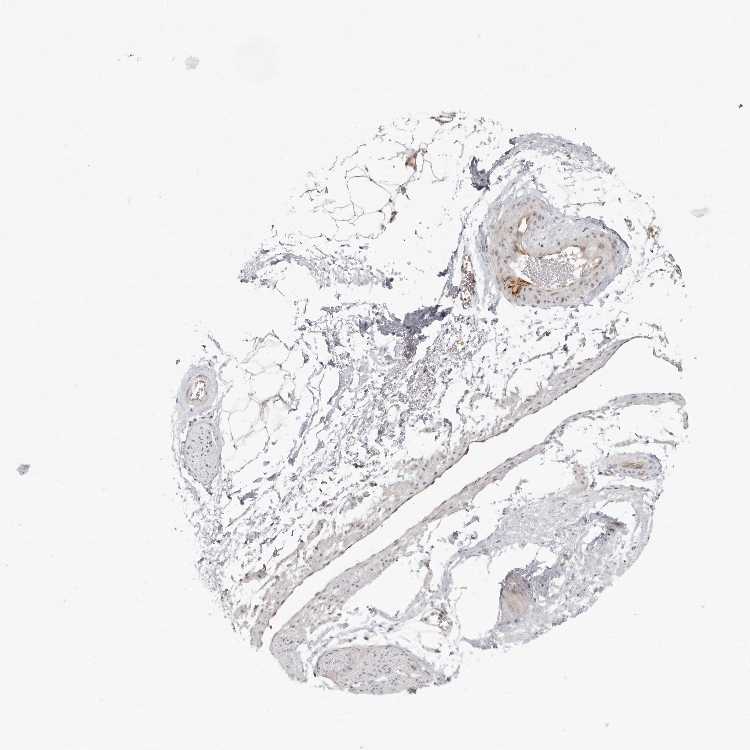

SOFT TISSUE 1 - Antibody stainingi

Antibody staining in the annotated cell types in the current human tissue is reported as not detected, low, medium, or high, based on conventional immunohistochemistry profiling in selected tissues. This score is based on the combination of the staining intensity and fraction of stained cells.

Each image is clickable and will lead to virtual microscopy that enables deeper exploration of all samples and also displays staining intensity scores, fraction scores and subcellular localization as well as patient and tissue information for each sample.

Antibody HPA029215Antibody HPA049694

Chondrocytes -Not detected

Fibroblasts MediumLow

Peripheral nerve Not detected-

SOFT TISSUE 2 - Antibody stainingi

Peripheral nerve -Not detected